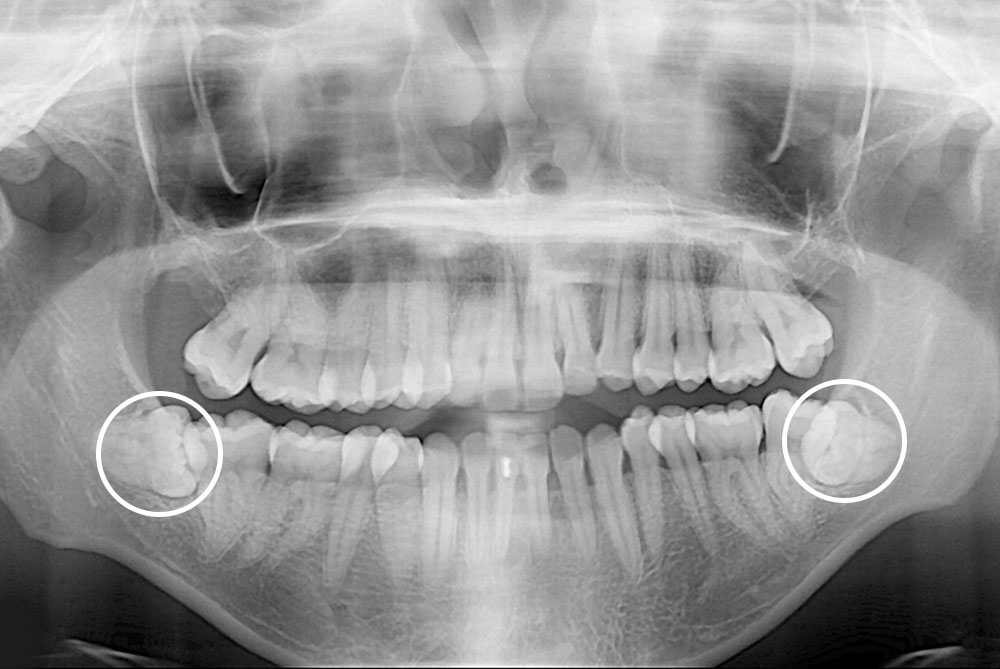

[사랑니] 매복 사랑니 발치

치료전 : 2019-04-15